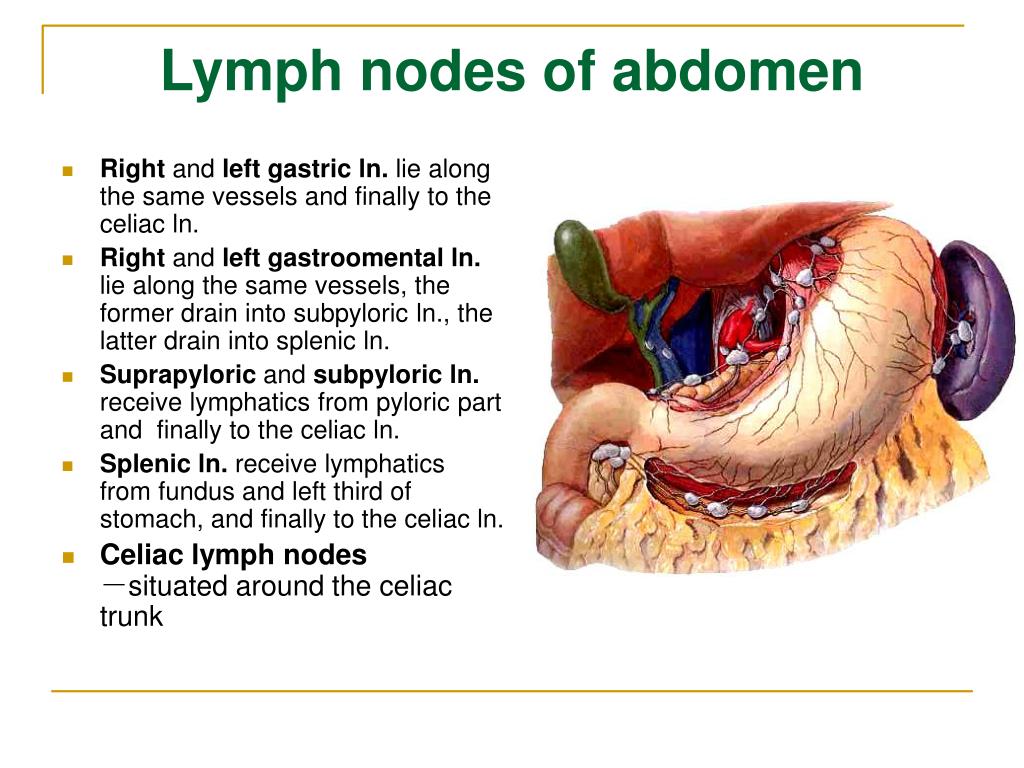

Upper Abdominal Lymph Nodes

mavink.com

mavink.com

Abdominal Lymph Nodes | SEER Training

www.training.seer.cancer.gov

www.training.seer.cancer.gov

lymph nodes abdominal celiac cavity visceral seer training wikidoc pyloric anatomy gastric